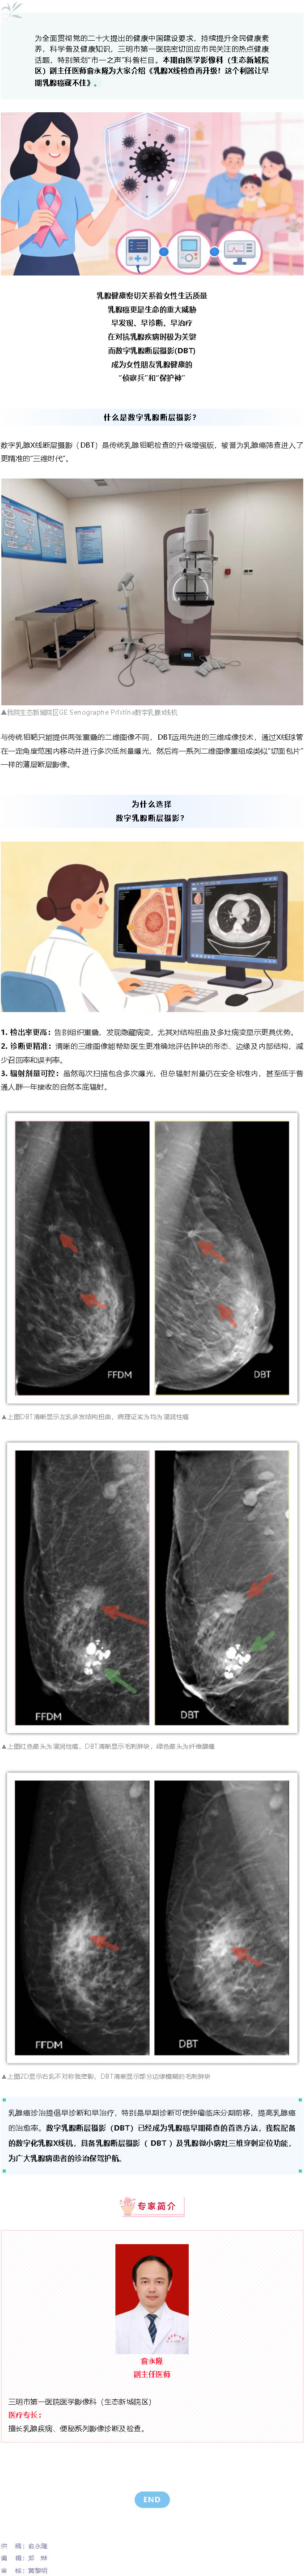

市一之声 ▏俞永隆:乳腺X线检查再升级!这个利器让早期乳腺癌藏不住